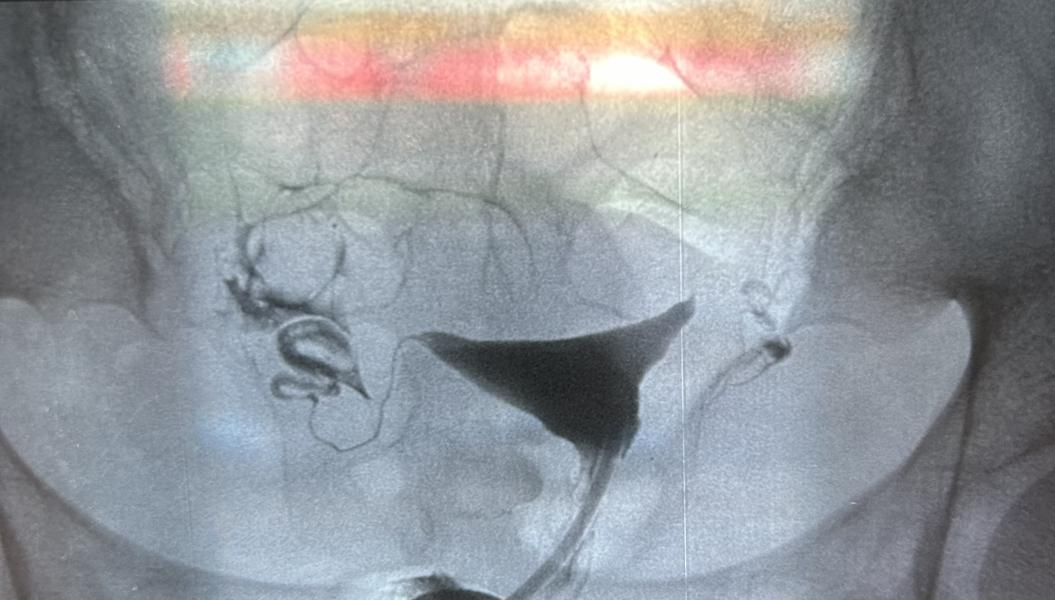

2 месяца назад я проходила гистеросальпингографию, тогда мне сказали обе трубы хорошо проходимы, была у Алмаса Курмангалиевича, он посмотрел снимок сказал левая сторона не проходима. У меня тоже были сомнения когда получала снимок, и переспросила у врача она мне в ответ сказала что, по трубам жидкость хорошо прошла. В прошлом году проверяла по узи, тогда тоже сказали проходимы. Теперь сижу, настроения ноль, получается у меня и так спкя и аноовуляция плюс теперь одна труба непроходима.